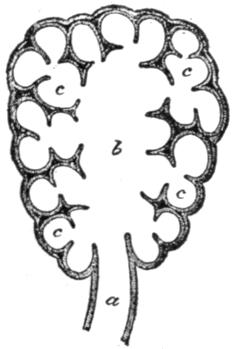

| VI. | The Respiration | H 70 |